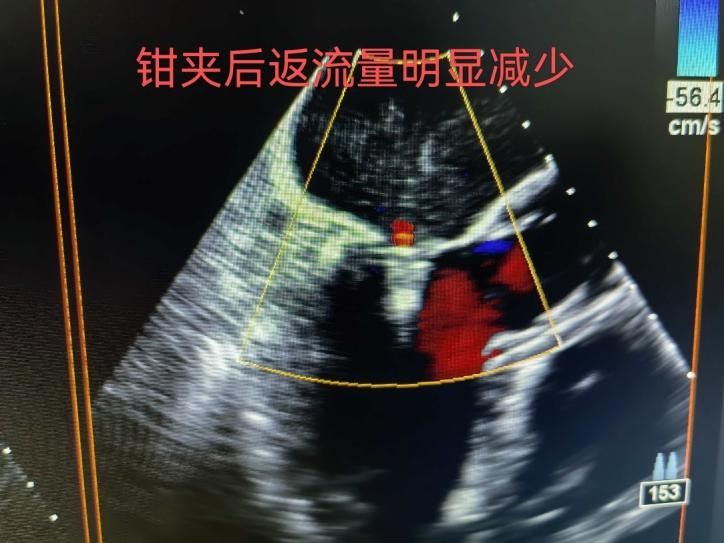

手術(shù)于11月4日下午進(jìn)行,通過股靜脈穿刺送入夾合器,在食道超聲實(shí)時(shí)引導(dǎo)下,精準(zhǔn)植入2枚瓣膜夾修復(fù)二尖瓣。整個(gè)過程歷時(shí)約2小時(shí),術(shù)中出血量?jī)H50ml。術(shù)后次日,患者即可下床活動(dòng),復(fù)查顯示EF提升至46%,二尖瓣返流面積縮小至3.0cm2,左心房縮小至66mm,胸悶、氣短癥狀明顯緩解。